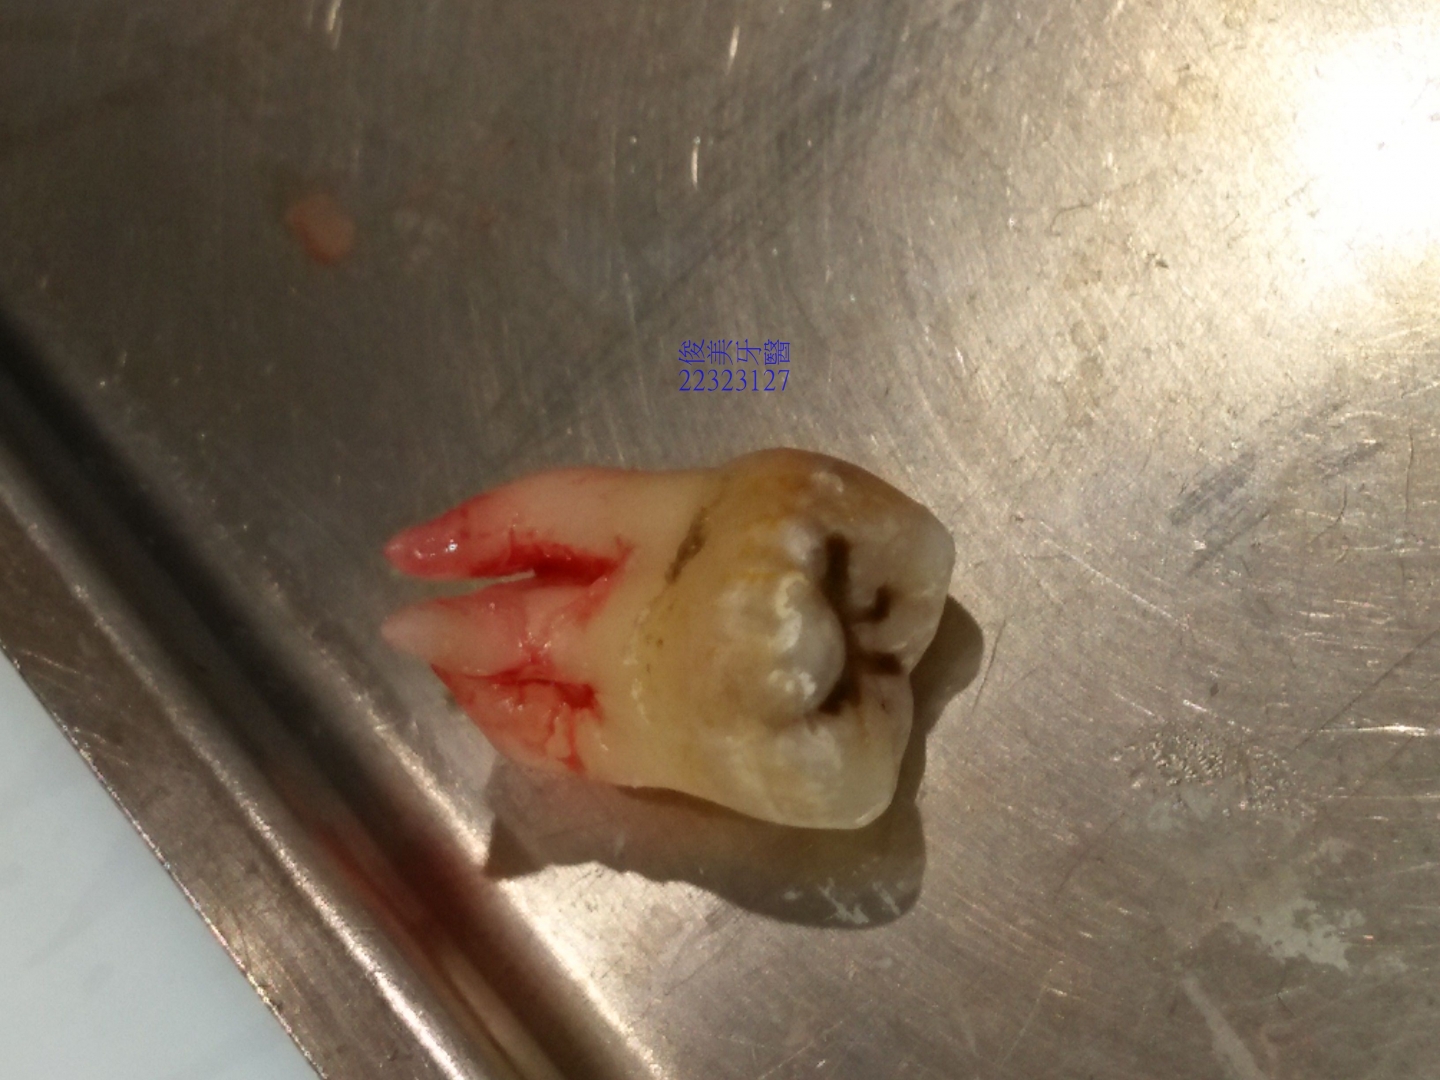

患者當下就決定拔左上智齒,因為實在是牙縫太會塞了,不到1分鐘,牙齒就已經拔完了。

患者有點驚訝,這麼快..................

且沒有感覺。

牙根彎曲的很厲害,表示沒有足夠的空間可以生長,

牙齒明顯清潔不良,所以應該要在18歲左右及早處理,以免後患無窮。